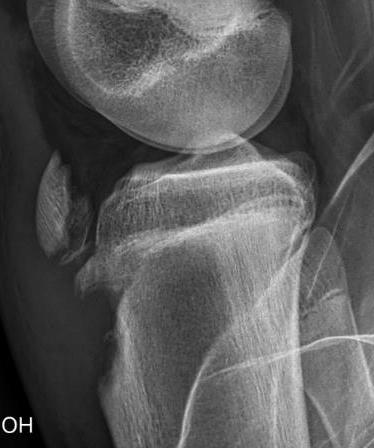

Ogden Classification

A: Undisplaced

B: Displaced

| Type I | Type II | Type III | Type IV |

|---|---|---|---|

| Avulsion distal tibial tubercle | Extension into tibial physis but not into knee joint | Extension across tibial physis and into knee joint | Extends posteriorly across tibial physis |

| Disrupts extensor mechanism | Disrupts extensor mechanism |

Disrupts extensor mechanism Disrupts articular surface Disrupts growth plate |

|

Associated Osgood-Schlatter Second most common |

Most common Risk of compartment syndrome |

Risk of compartment syndrome |

Type IB

Type IIB

Type III

Comminuted Type III